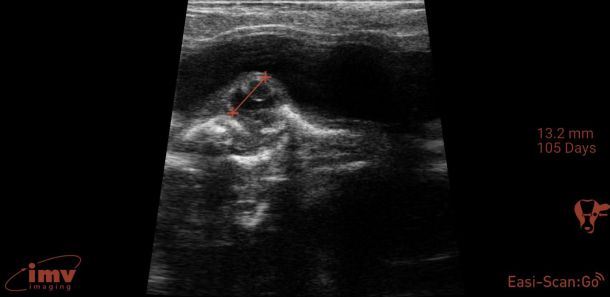

Detailed ultrasonography can detect pregnancy from 22-24 days post-insemination but due to higher rates of loss and inconsistency in quickly detecting the foetus, it is advisable that ultrasonographic pregnancy diagnosis at 28-30 days post-insemination is performed as it becomes very reliable (see Photo 2)2. At this point, the embryo becomes visible as a small, echogenic (white) structure suspended within the black (anechoic) uterine fluid2. Beyond this point, ageing is performed by either measuring or ‘eyeballing’ foetal crown-rump length, head or trunk diameter, head length or eyeball diameter (for references lengths see Table 1)6,7. Modern ultrasound machines will automatically give an estimated days in-calf, if the image is frozen and a distance is measured, but the author finds that the grid function (where a box represents 10mm) is a more useful way to eyeball these measurements without having to freeze the image. Thus thinking in boxes allows the user to reliably age using the crown rump length up to day 60 and then using head diameter and/or eyeball from days 60-150 days (see Photo 3). Measuring the placentomes is not a very reliable method to accurately age owing to the fact that placentome size will vary depending on where in the horn it is located, with smaller placentome being at the edge of the horns2.